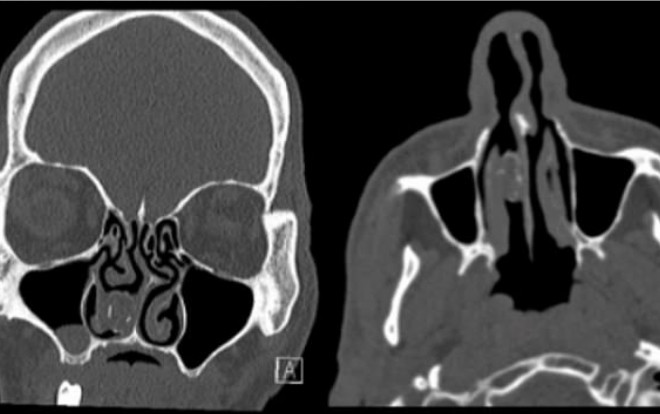

Các bác sĩ ở Úc đã tiến hành chụp CT não, sau khi người đàn ông đến bệnh viện và phàn nàn về chứng đau đầu của mình - một trong những triệu chúng phổ biến của sỏi mũi. Qua ảnh chụp, các bác sĩ thấy một vết thương màu xám với kích thước 1,9cm x 1,1cm trong khoang mũi phải của anh ta. Sau đó anh ta được chuyển đến khoa tai mũi họng tại Bệnh viện Westmead, Sydney.

Hình chụp CT của người tù nhân “đãng trí”